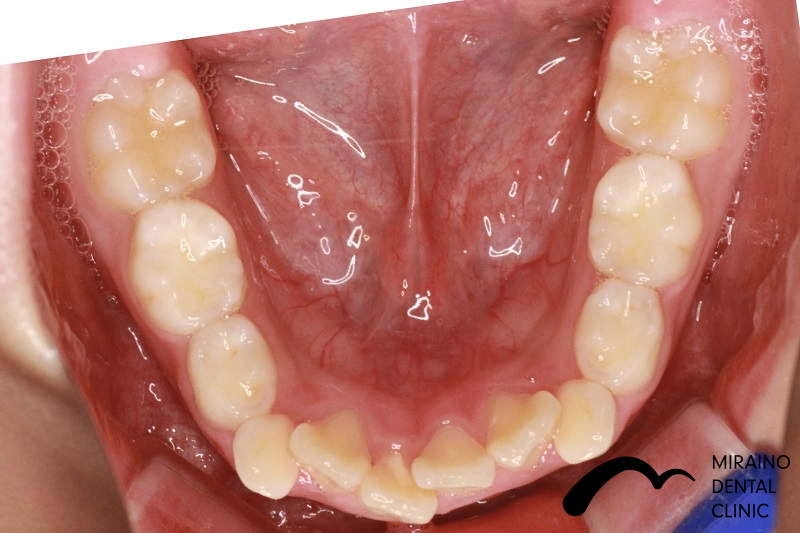

叢生(ガチャガチャ・ガチャ歯)①

| 施術名 | マウスピース矯正(インビザライン) |

| 施術の内容 | 歯科矯正でも目立ちにくい新しい矯正方法です。 透明に近いマウスピース型の矯正装置(アライナー)のため、歯に装着しても目立つことなく歯並びを矯正することが出来ます。 また、一人ひとりの合わせて矯正装置を作製いたします |

| 治療費 | インビザライン990,000円 |

| 考えられるリスク、副作用 | 疼痛・咬合時痛を生じる事があります。 時間経過とともに治ります。 |

| 考えられるリスク、副作用[矯正] | 継続使用により緩んだり、外れやすくなる事があります。 割れたり壊れたりする事があります。 諸々の事情により、治療期間が当初よりも伸びる事があります。 所定の装着時間22時間を守って頂けない場合、治療計画どおりに治らない可能性があります。 歯が動く際に、痛みが出る事があります。 矯正期間中は虫歯や歯周病のリスクが高まりますので、しっかりとしたケアが必要です。 歯の移動に伴う歯肉退縮や歯根吸収が起こる事があります。 インビザライン・システム(invisalignR)は、アメリカのアラインテクノロジー社より提供されている、カスタムメイドの矯正装置ならびに、これを用いた治療システムを指します。 インビザラインを用いた治療は保険適用外の自由診療となります。 厚労省の認可(医薬品医療機器等法上の承認)は得ていないため、まだ明らかになっていないリスクが存在する可能性があることをご了承ください。 |

| 全て | 必ずしもご希望通りの見た目にならない事があります。 |